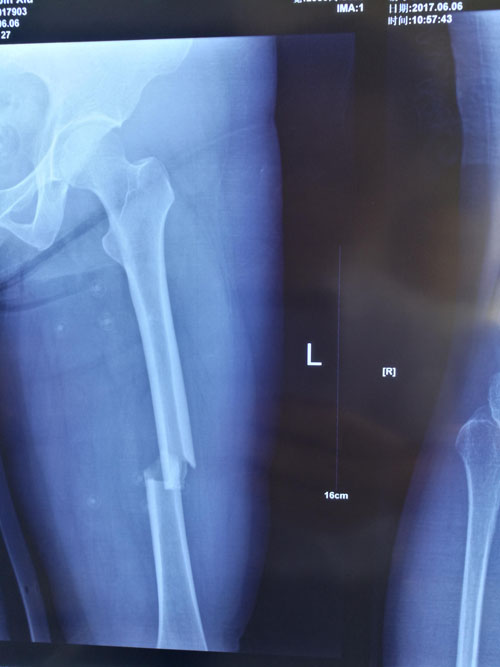

典型病例:閉合復(fù)位髓內(nèi)釘治療股骨骨折,創(chuàng)傷小、出血少,骨折愈合快。